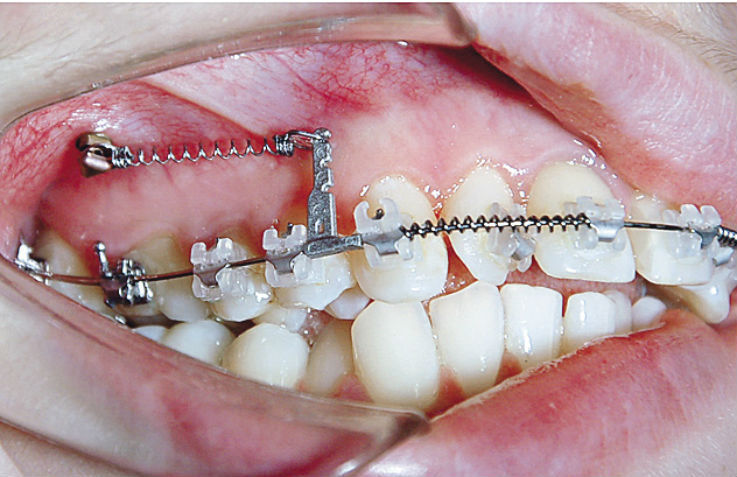

Применение ретрактора в ортодонтии

Ретрактор считается одним из важных помощников в современной ортодонтии.